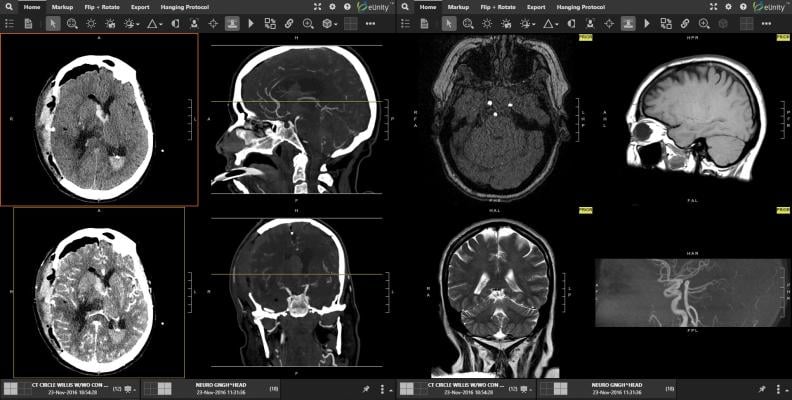

April 11, 2024 — Mach7 Technologies, a company specializing in innovative medical imaging and data management solutions for healthcare organizations, announced its participation in the Veterans Health Administration's (VHA) National Teleradiology Program (NTP). As part of this multi-phased contract, Mach7 will provide its well-established Vendor Neutral Archive (VNA) and industry leading eUnity Enterprise Diagnostic Viewer to help form the core workflow of the NTP NextGen Picture Archiving and Communication System (PACS) architecture.

The VHA offer was awarded to Frontier Acquisitions, LLC, which is a prime vendor based out of San Antonio, Texas. Frontier selected Nuance to provide Voice Recognition and Diagnostic Radiology Workflow, Mach7 Technologies as the Diagnostic Viewer and Vendor Neutral Archive, Blackford (blackfordanalysis.com) to incorporate Adaptive Intelligence (AI) Technology and Microsoft Corporation to provide it's Azure Cloud Computing Platform.

Within the framework of this implementation, Mach7 brings to the forefront core market differentiators and value around the adoption of advanced imaging technologies that provide unique independence and long-term sustainability. The VHA NTP award, through Frontier, is a tremendous opportunity for Mach7 to deliver and showcase its unique Enterprise Imaging Solution with strong interoperability to the VHA's existing and newly deployed imaging systems. This distinctive enterprise-driven architecture will grant the VHA the ability to leverage its existing medical systems while not being tied to a single vendor's proprietary ecosystem.